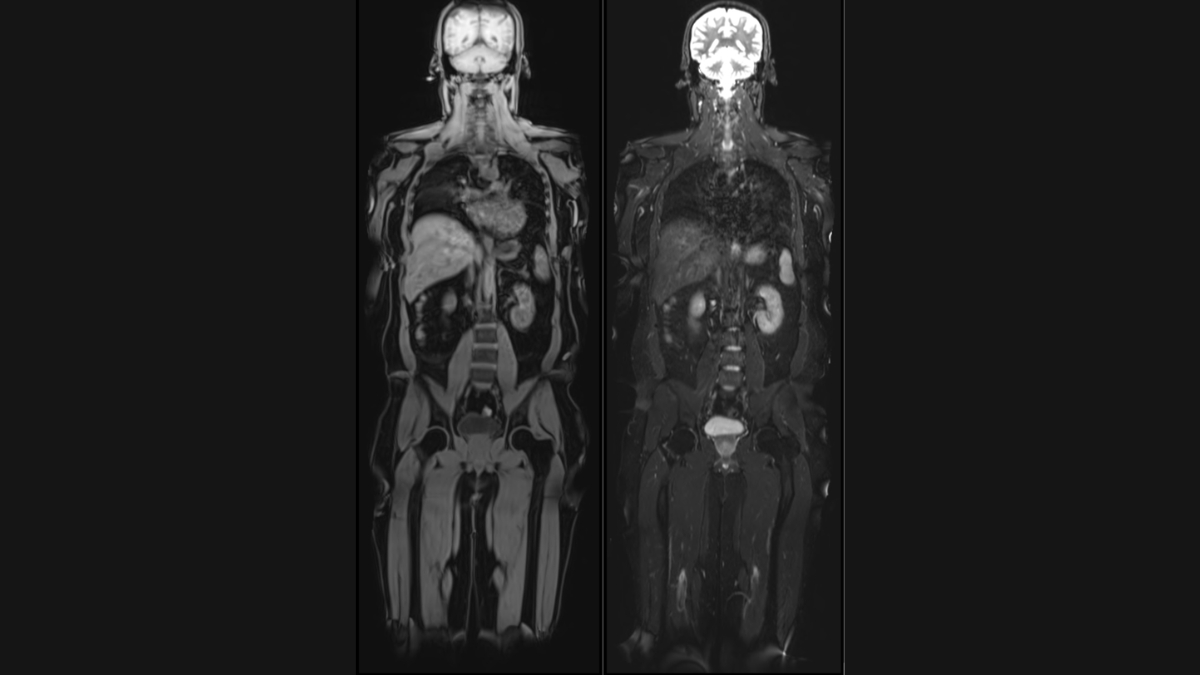

Vital Full Body MRI aims to detect potential health issues at their earliest stages, including early-stage cancers, aneurysms, spinal degeneration, disc bulges, and abnormalities in the brain, abdomen, and chest. The scans utilize cutting-edge technology to provide detailed, high-resolution images, enabling early diagnosis and intervention, thereby improving treatment outcomes.

Unique offerings of Vital MRI are – Brain volume analysis, Liver fat and Visceral fat quantification by MRI and Calcium scoring CT to assess heart attack risk. Brain volumetry analysis, generating a ‘Brain Age’ report that compares an individual’s brain health to their chronological age. This valuable insight can help individuals understand their cognitive well-being and take proactive measures to maintain brain health and prevent dementia.